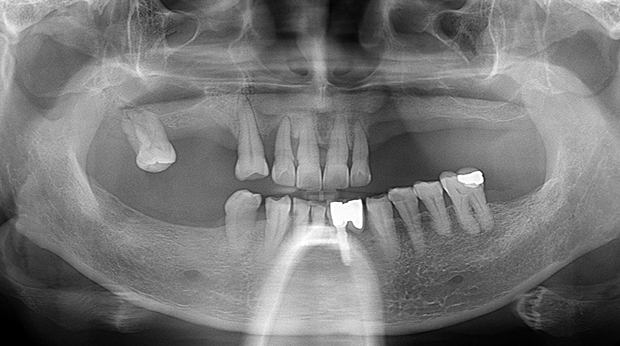

임플란트와 사랑니 발치는 외과적 시술로 잇몸을 절개하는 외과적 시술은

짧으면 짧을 수록 시술 후 붓기와 통증이 최소화됩니다.

치과의사 경력 14년차 구강외과 전문의가 빠르고 안전하게, 아프지 않게 수술해 드립니다.